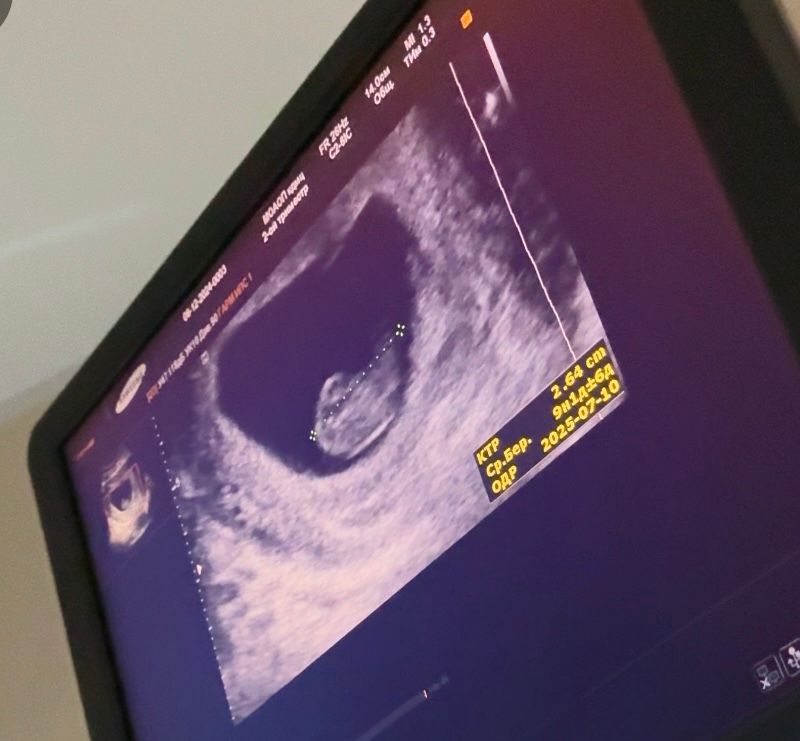

УЗИ 9 недель , не похож на малыша

Виктория, ИзображениеЭто 10 недель, он просто лежит и уже смахивает на человека , но не видно хорошо пальчиков и всего остального. Изображение Это с приложения 9 недель , вы видите пальчики на руках??? Я с вами спорить не буду , более информативно смотреть когда больше 11

Виктория, в ту беременность , я делала на ранних сроках почти каждую неделю , из-за отслойки, именно гибель плода никак не связана, с узи, это уже было на более позднем сроке. В эту беременность из-за страха , делала на 5,6,9,11,12 ну и сам скрининг. Аппараты действительно все разные . В одном вообще мне намерили ктр на 9 недель , хотя у меня было 11. Но всех этих малышариков я все время смотрела и самое более похожее прям мини человечек это 11 недель , как по мне. Спасибо, вам тоже всего доброго.